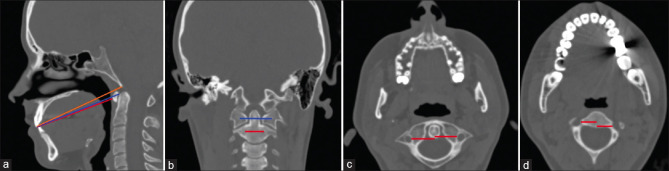

Methods: The study was performed using cranial computed tomography images of 200 patients. These patients consisted of 100 men and 100 women. The age range of the individuals included in the study varies between 20 and 80. In our study, the parameters measured and recorded in the coronal, sagittal, and axial plane.